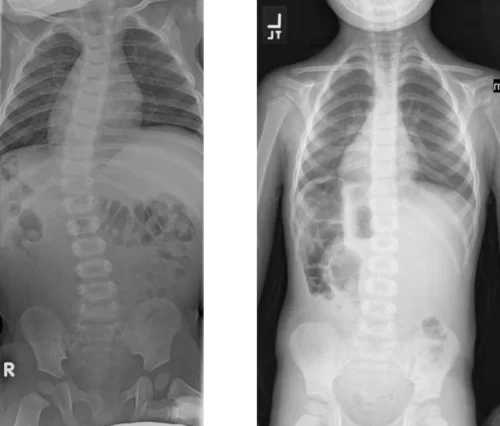

كيف يتابع الأطباء نجاح العلاج؟

يستخدم الأطباء زاوية كوب لقياس درجة الانحناء. وبعد كل جلسة تجبير، يطلب الطبيب صورة أشعة لتقييم التغيرات. وكلما انخفضت الزاوية تدريجيًا، دل ذلك على استجابة العمود الفقري للعلاج.

على الرغم من فعاليته الكبيرة، إلا أن بعض الحالات لا تستجيب بالشكل المطلوب. فعندما يستمر الانحناء في التفاقم رغم الجبائر، قد يقترح الطبيب اللجوء إلى الجراحة. ومع ذلك، يُعتبر التجبير التسلسلي دائمًا المرحلة الأولى والأكثر أمانًا، لأنه يُعطي فرصة حقيقية لتصحيح الاعوجاج دون تدخل جراحي.